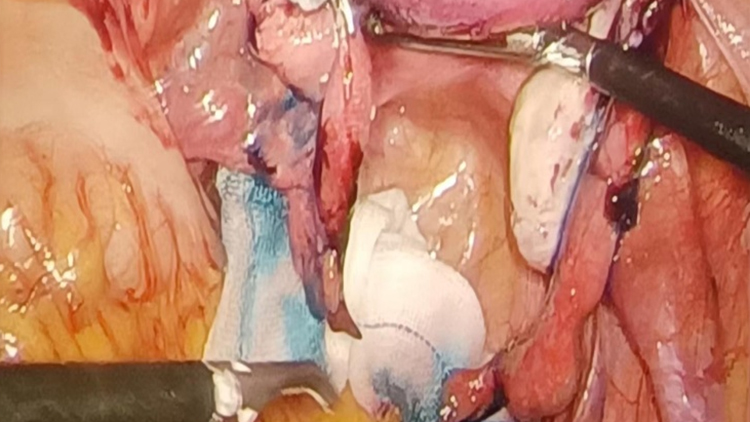

家住来凤县翔凤镇的钱女士,34岁,2009年于浙江玉环行剖宫产术,2011年于外院行剖宫产+双侧输卵管结扎术,2022年5月11日来我院就诊,因“双侧输卵管扎术后11年,要求复通”入院。入院后完善检查,排除手术禁忌,积极完善术前准备,于2022年5月14日在麻醉下行腹腔镜下+盆腔粘连分解+输卵管吻合+输卵管通液,术中见子宫前壁与盆壁致密粘连,大网膜与左侧腹壁,分离粘连,双侧输卵管可见结扎疤痕,行美兰通液,伞端未见美兰流出,分离盆腔粘连,行腹腔镜下输卵管吻合,再次输卵管美兰通液,伞端可见美兰流出,术中失血约20ml,手术顺利。